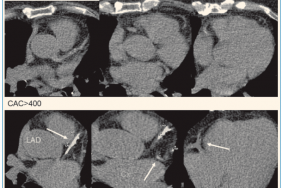

Selon le dégré de calcification on a établi cinq catégories :

- CAC-score = 0 Pas d’athérome calcifié, le risque cardiovasculaire est minimal

- CAC-score = 1-10 Peu de plaques calcifiées

- CAC-score = 10-100 Calcifications coronaires modérées

- CAC-score = 100-400 Calcifications coronaires marquées

- CAC-score > 400 Importantes calcifications coronaires

Un score supérieur à 400 correspond à un risque cardiovasculaire élévé (taux d’évenements >20 % à 10 ans) chez des sujets sans symptômes et sans maladie coronaire connue. Des examens complémentaires auprès d’un cardiologue, et notamment une coronarographie pour vérifier l’irrigation des artères coronaires sera proposé. Ces patients doivent en outre bénéficier d’un suivi régulier avec un contrôle des facteurs de risque cardiovasculaires comme le sevrage tabagique, le contrôle du poids, la pratique d’une activité physique régulière, des chiffres tensionnels et glycémiques stables et optimaux.